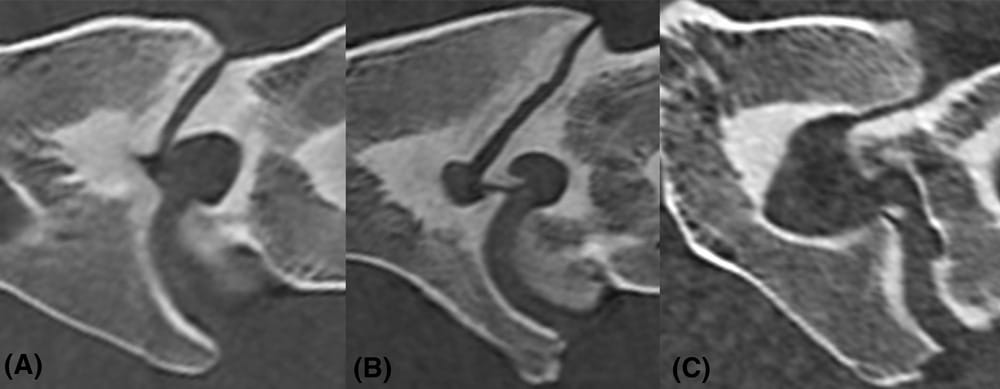

Examples of intervertebral foramina narrowing. A, Sagittal image at C6-C7. Maximum narrowing at the cranial third due to enlargement of the caudal AP of C6. B, Sagittal image at C6-C7. Maximum narrowing at the middle third due to enlargement of the cranial AP of C7. C, Sagittal at C7-T1 is shown. Maximum narrowing at the caudal third due to enlargement of the cranial AP of T1. Note the mineral attenuation along the dorsal aspect of the intervertebral disk space. These images are from different horses and were acquired with a large bore (90 cm diameter) 16-slice third-generation CT unit (Aquilion LB, Toshiba, Brussels, Belgium) associated with a moving gantry positioned in a pit (Qualibra, Berlin, Germany) and with the horses placed in dorsal recumbency. Helical acquisition (135 kVp, 420 mA, collimator pitch = 0.94, detector pitch = 15, 1 mm slice thickness, 1 mm reconstruction interval, matrix size = 512×512 pixels and field of view = 550 mm), bone reconstruction algorithm, bone window (Level = 1000 HU; Width = 3500 HU) and multiplanar reconstruction with 1 mm slice thickness were used for all measurements. AP: articular process.